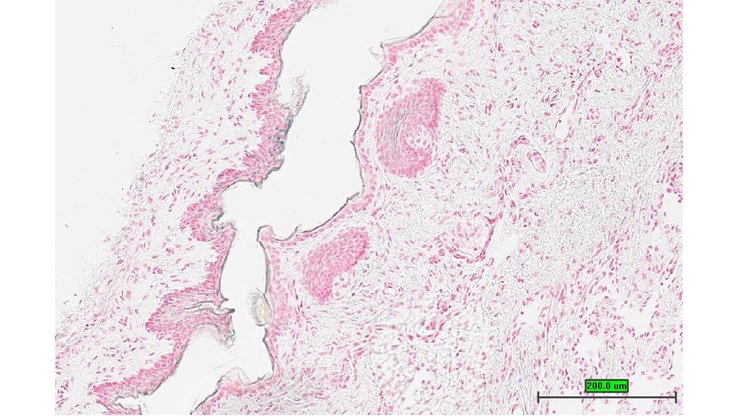

TS28: esophagus Present UC Davis_1860065

TS28: esophagus Present UC Davis_1860066

TS28: esophagus Present UC Davis_1860106